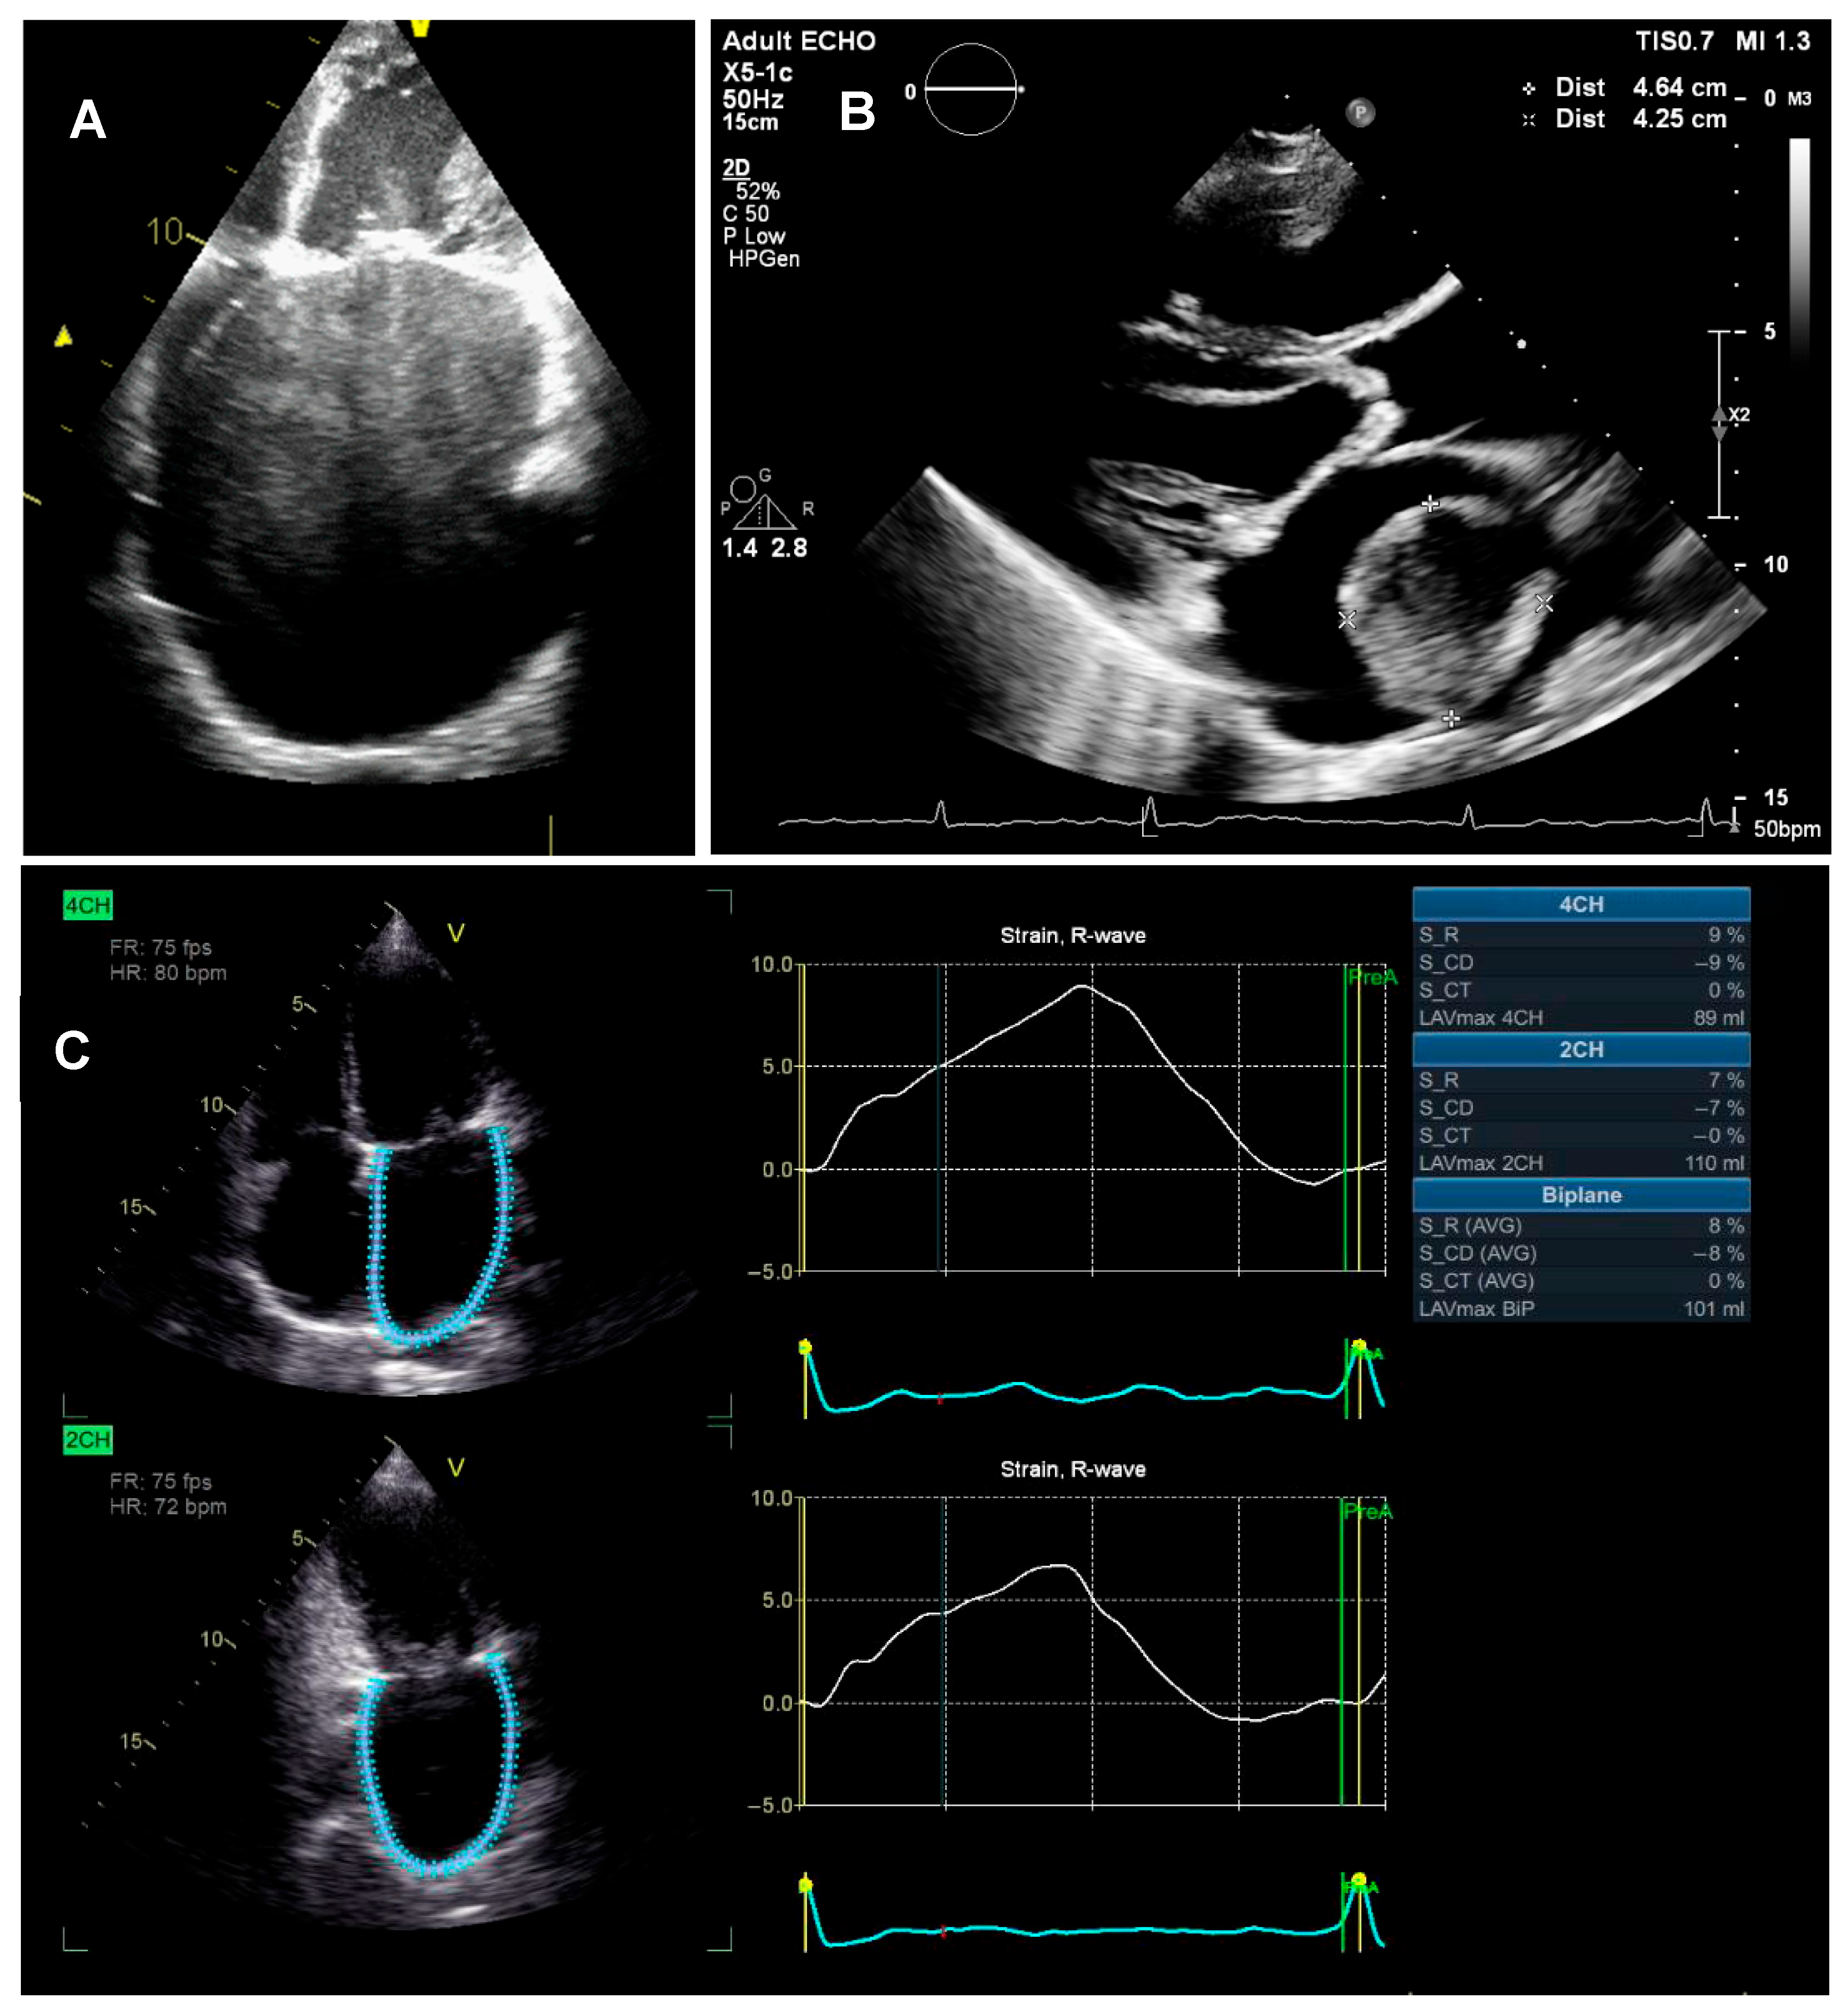

4.1.4. LA Dysfunction

- Elkareem, T.S.A.; Ahmed, T.A.; Mohamed, L.A. Left Atrial Remodeling in Patients with Severe Rheumatic Mitral Stenosis and Sinus Rhythm Using Two-Dimensional and Three-Dimensional Speckle Tracking Echocardiography. Cardiol. Res. 2023, 14, 142–148. [Google Scholar] [CrossRef]

- Amshala, R. Left Atria Function in Mitral Stenosis: Tissue Doppler Strain Imaging Before and After Balloon Mitral Valvotomy. J. Cardiovasc. Dis. Res. 2022, 13, 1299–1308. [Google Scholar]

- Soesanto, A.M.; Desandri, D.R.; Haykal, T.M.; Kasim, M. Association between late gadolinium enhancement and global longitudinal strain in patients with rheumatic mitral stenosis. Int. J. Cardiovasc. Imaging 2019, 35, 781–789. [Google Scholar] [CrossRef] [PubMed]

- Galli, E.; Lancellotti, P.; Sengupta, P.P.; Donal, E. LV mechanics in mitral and aortic valve diseases: Value of functional assessment beyond ejection fraction. JACC Cardiovasc. Imaging 2014, 7, 1151–1166. [Google Scholar] [CrossRef]

- Bilen, E.; Kurt, M.; Isik, T.; Ekinci, M.; Kaya, A.; Bayram, E.; Simsek, Z.; Tanboga, I. PP-115: Severity of Mitral Stenosis and Left Ventricular Mechanics: A Speckle Tracking Study. Int. J. Cardiol. 2011, 147, S128. [Google Scholar] [CrossRef]